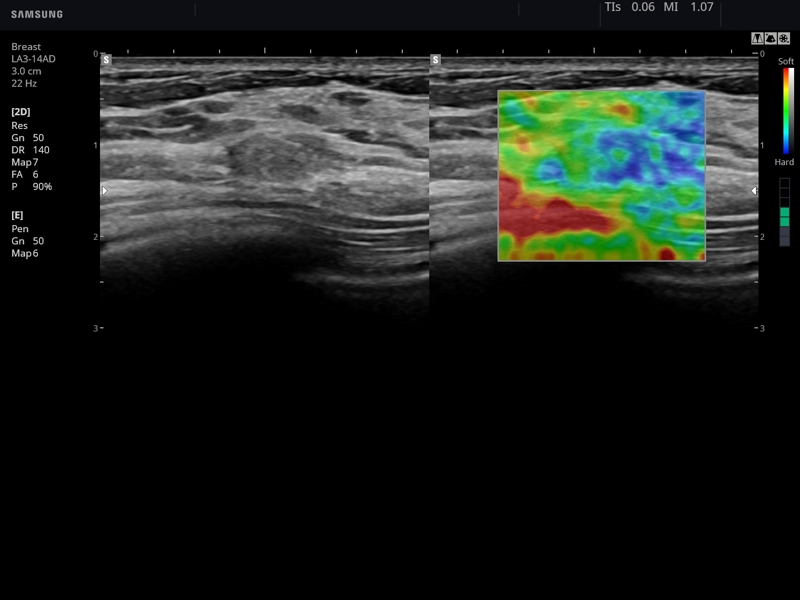

Примеры клинических изображений УЗИ аппарата hs60 A-RUS (Samsung Medison)

- Модуль Elastoscan - программы эластографии (качественная оценка) для исследований щитовидной железы, молочной железы у женщин и предстательной железы у мужчин.

- Mодуль E-Strain - программа количественной оценки эластичности тканей по выбранной зоне (необходим модуль Elastoscan).

- Модуль S-Detect Breast - программа автоматического обнаружения и анализа образований молочной железы у женщин, измерение и классификация по системе BI-RADS.